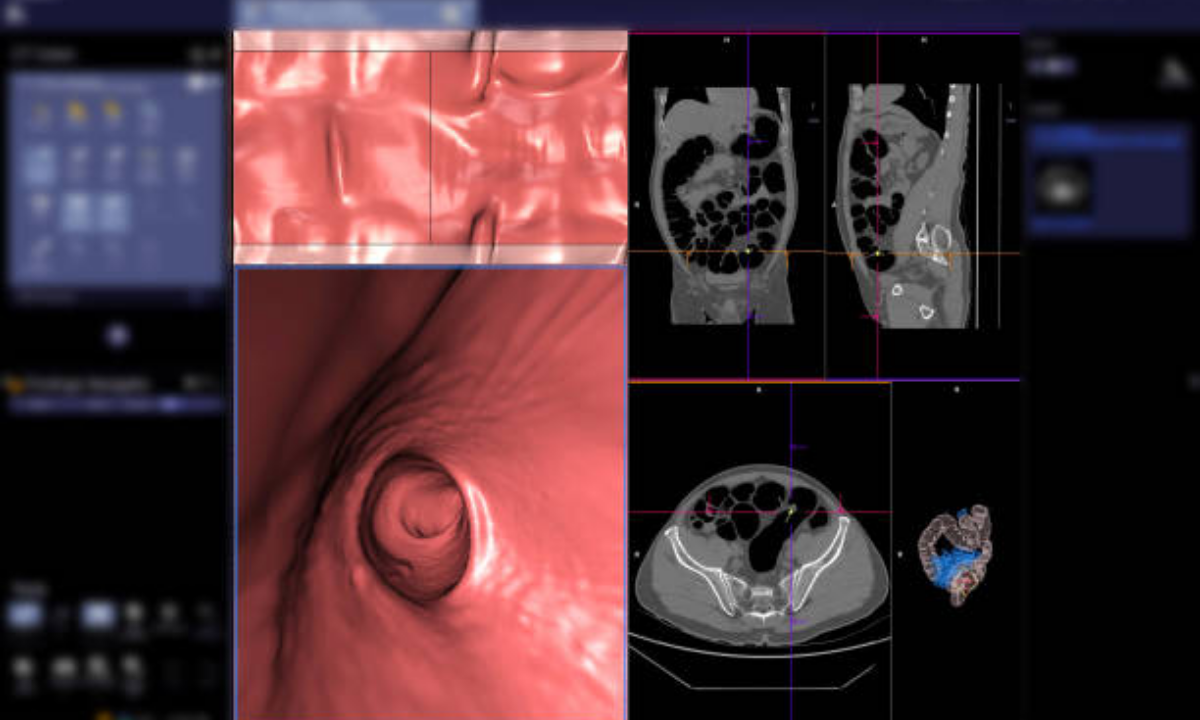

Unlike traditional colonoscopy, which uses a flexible tube inserted into the colon, a CT colonoscopy uses advanced imaging to create detailed 3D pictures of the large intestine. This makes it far more comfortable, faster, and equally accurate for early diagnosis.

Traditional colonoscopy uses a scope with a camera, while CT colonoscopy or virtual colonoscopy relies on computed tomography imaging to produce similar views without the discomfort of inserting a tube.

A Colonoscopy CT Scan uses computed tomography to create 3D cross-sectional images of the colon and rectum. The process is quick, non-invasive, and usually takes around 15–20 minutes.

With this test, doctors can identify polyps, tumors, inflammation, and structural abnormalities, all without sedation or recovery time.

| 4. Image Reconstruction | The system builds 2D and 3D images for review. |

| 5. Colonoscopy Report | The radiologist analyzes findings like polyps, tumors, or inflammation and prepares a report for your doctor. |